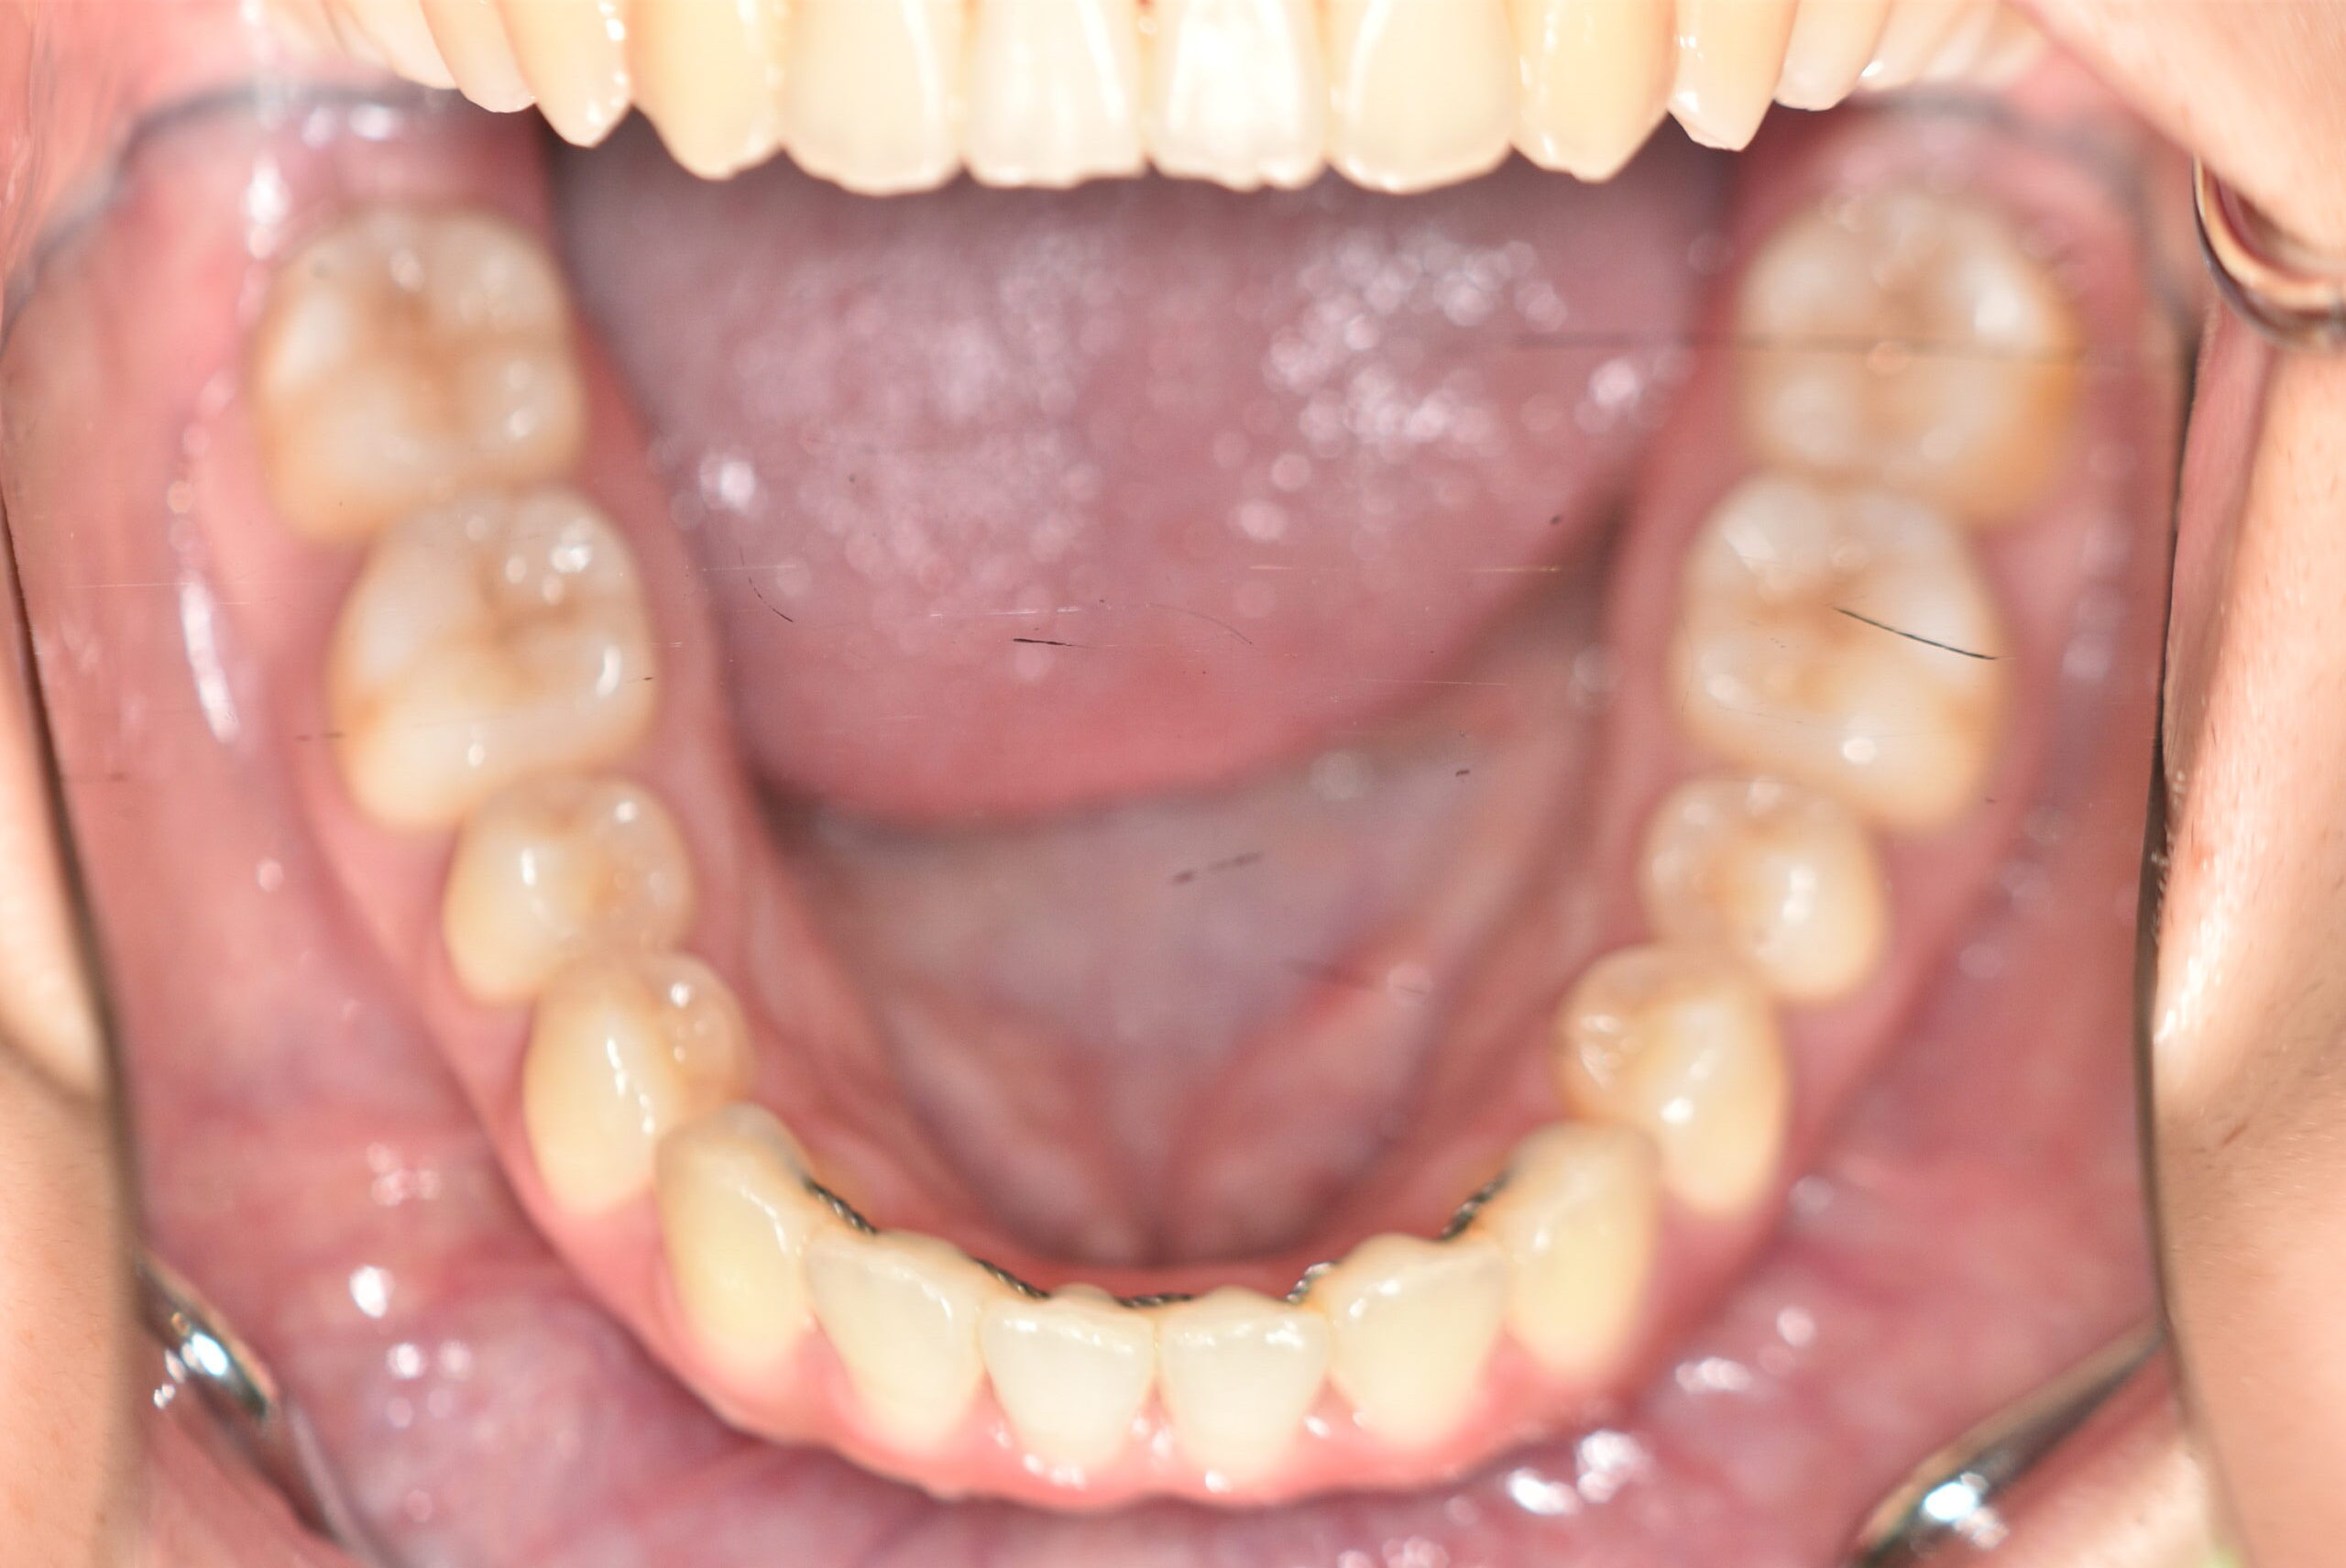

初診時

治療内容の詳細 初診時17歳の女性で、かみ合わせが悪く少しガタガタしていることをを気にされ来院されました。

検査の結果、上下顎叢生を伴うアングル1級不正咬合と診断しました。

治療としては、非抜歯の上、マウスピース型矯正装置(インビザライン)で歯の配列を行いました。